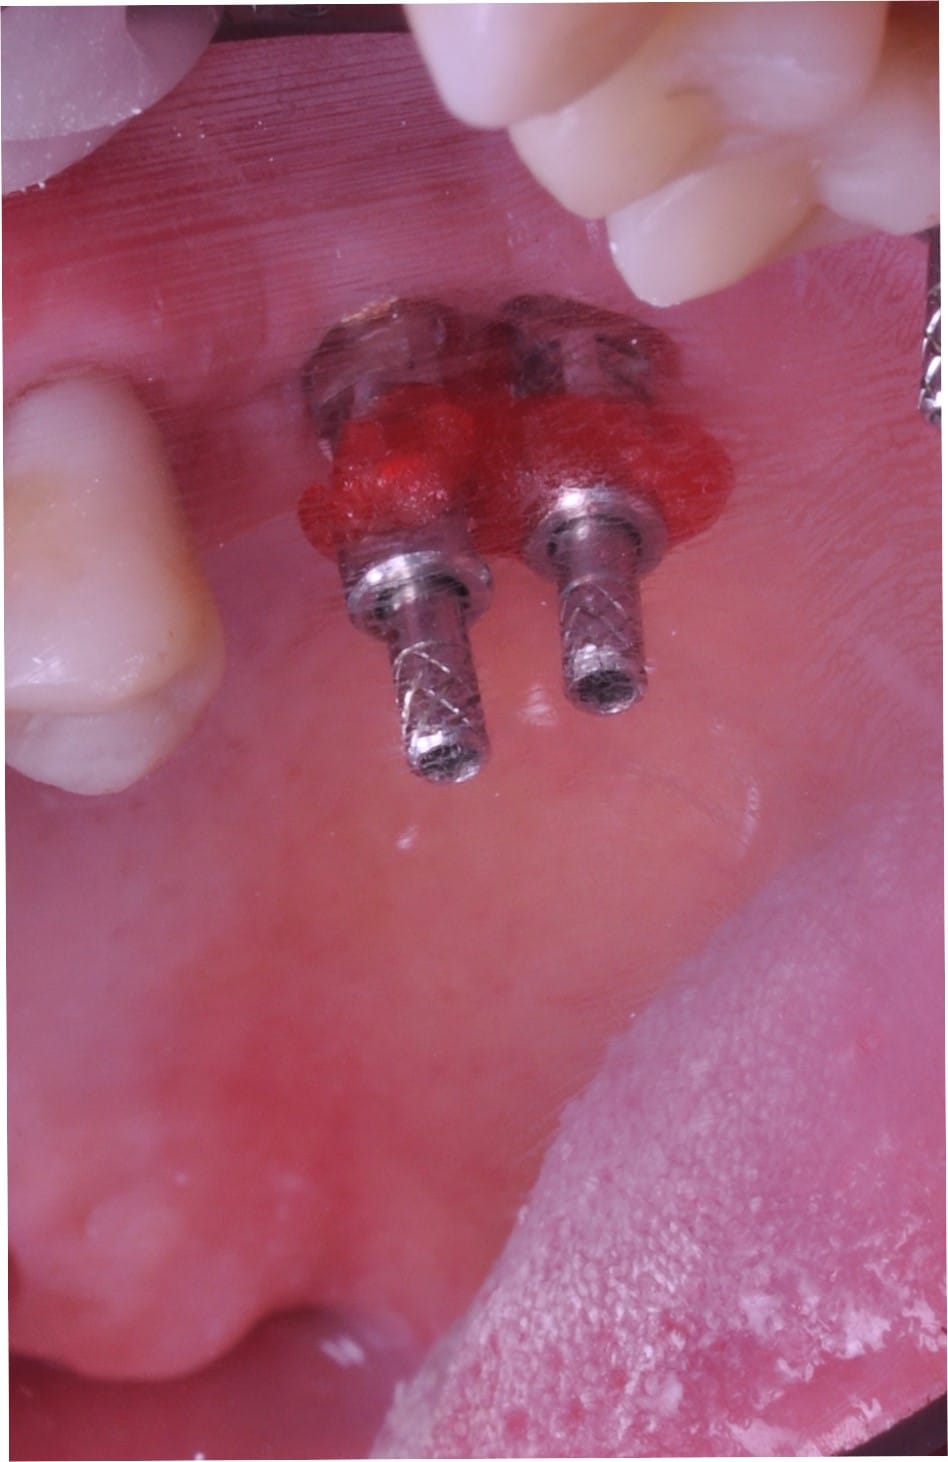

A doua etapă, inserarea implanturilor, a fost realizată după 6 luni.

Împreună cu pacientul, am optat pentru inserarea implantelor cu ajutorul ghidului chirurgical pentru a plasa implantul în poziția protetică ideală și pentru a permite realizarea coroanelor insurubate pe implant. A fost efectuată scanarea digitală a arcadelor și a ocluziei pacientului, iar împreună cu tehnicianul radiolog de la DigiRay a fost suprapus fișierul .stl al amprentei digitale peste fișierul .dcm de la CBCT, utilizând software-ul 3Shape.

S-a planificat individual poziția și axul de inserție al fiecărui implant.